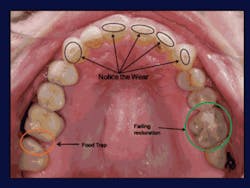

It sounds like such a simple solution, but imagine the following scenario: A new patient goes through a thorough diagnostic process in your office. After seeing images of his or her teeth and soft tissue on a high-resolution monitor, the two of you discuss any issues that could stand in the way of optimal oral health while using the images as a reference. You and the patient discuss the pathology and numerous treatment options, and for the first time, the patient truly understands his or her dental situation and options. The patient seems eager to fix the problems, and although he or she may not go through treatment right away, when he or she does, the patient becomes your “partner” through the progression of care.

Taking images and then going through them with the patient allows most of us to see our patient’s oral cavity differently than by performing even the most thorough exam or viewing a well-mounted set of study casts. Enjoy feeling unhurried and take the time to evaluate the images along with your patients. You’ll be amazed at the difference this makes in how you plan treatment.